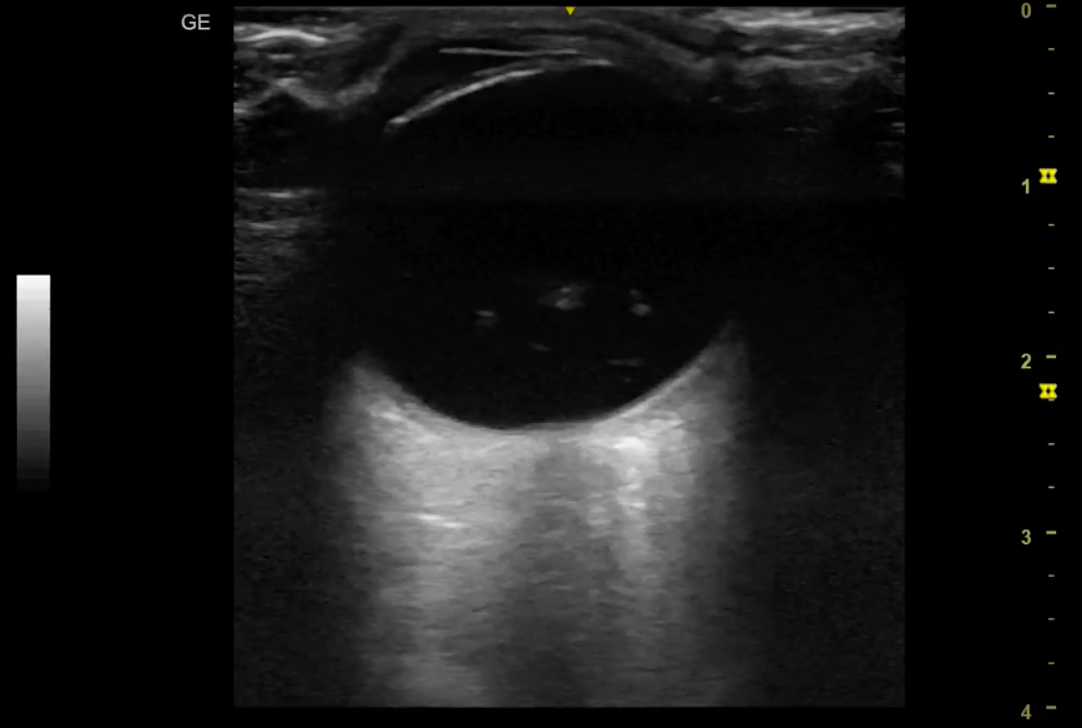

Hallazgos ecográficos

Se realiza ecografía ocular no reglada, donde se objetiva globo ocular anecoico con contenido heterogéneo hiperecogénico en polo posterior. Realce acústico posterior.

Desprendimiento de vítreo.

Tras el hallazgo ecográfico, se comenta el caso con Oftalmología de urgencias. Confirmar el desprendimiento de vítro del ojo derecho.